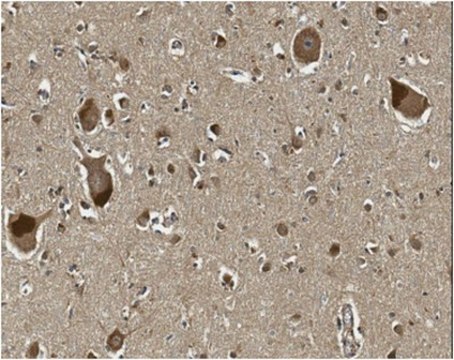

Immunohistochemistry Analysis: A 1:250 dilution from a representative lot detected Oligodendrocyte transcription factor 2 (OLIG2) in human cortical brain section tissue.